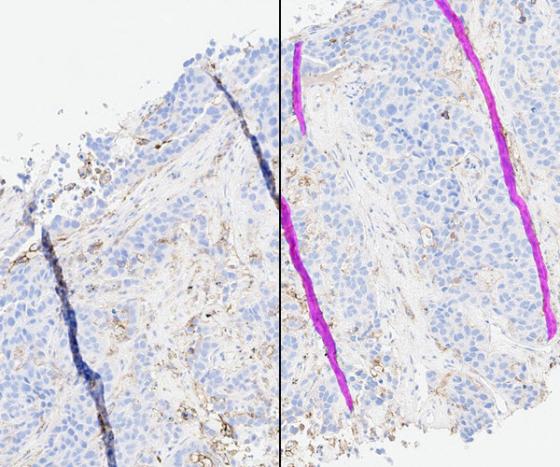

IHC digital slide (left) with SlideQC BF markup (right) highlighting tissue folds in magenta.

After selecting an image, view the H&E or IHC slide in the viewer and the SlideQC BF results. Results include overlays and quantitative results. The overlay highlights artifacts in magenta and acceptable tissue areas in cyan.